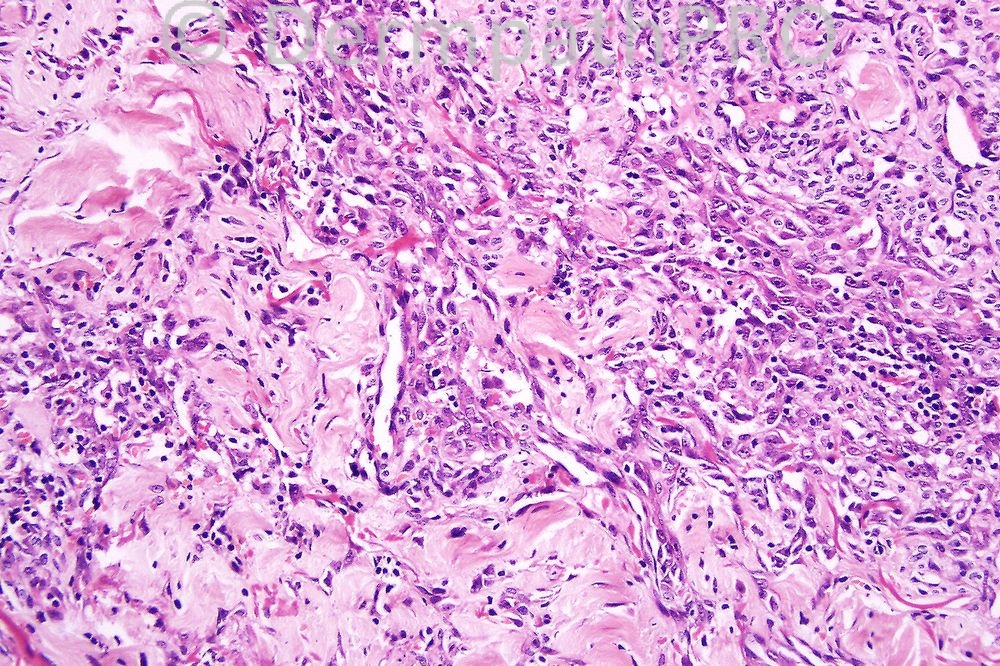

There is so much going on today that I thought that it would be best if I give answer early unless I forget. The lesion is a post radiation angiosarcoma of the breast. It is predominantly spindled cell type. Epithelioid examples are much more epithelioid and often have intracytoplasmic lumina. The only real differential diagnosis would be a "high grade" field from a KS but the endothelial cell atypia makes the diagnoses less problematical

I thought of angiosarcoma but I think it is the ordinary not the epithelioid variant..

MALIGANT VASCULAR TUMOUR SHOWING AUTO-ILLUMINATION. I FAVOUR ANGIOSARCOMA (EPITHELIOD).

Welcome back sir I wish you the best of luck at your new home. In this photo I can see areas of thickened collagen bundles in vicinity of a collection of epitheliod cells ,lymphocytes and proliferating vessels I suggest D.D of necrobiotic granulomas as GA,NBL OR rheumatoid nodule or I could be possibly out of track completely I ll eagrly wait for the correct answer!

epithelioid angiosarcoma